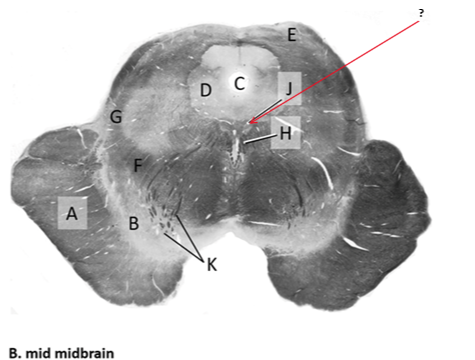

Name this and state its function.

Tectum.

Name this and its divisions+ function?

Substantia nigra.

Cerebral aqueduct.

Crus cerebri.

Medial Lemniscus.

Name this, what is it and state its function.

Lateral lemniscus.

Name this, state its function[2 marks] and how it goes about its function[4 marks].

Medial longitudinal lemniscus.

How?

Oculomotor nucleus.

Name this, state its function[3 marks] and cells involved contributing to function.

Periaqueductal grey.

Root fibres of Oculomotor nerves(CN III).